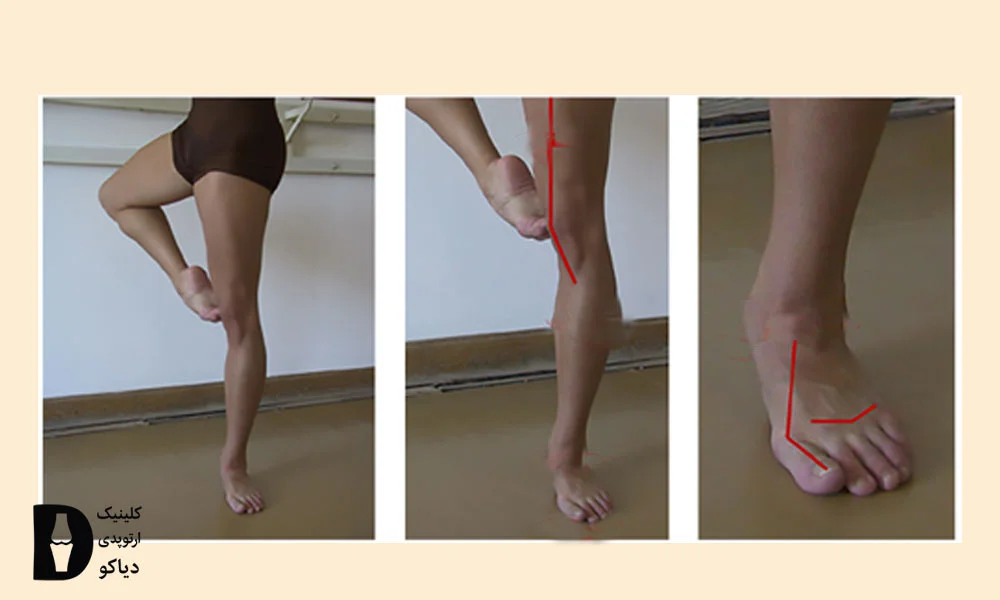

برای رانندگی طولانیمدت

بر اساس منابع بالینی فشار مداوم روی پا، علائم هالوکس والگوس را تشدید کند. یکی از مواردی که باعث فشار مداوم روی پا میشود، رانندگی است. این موضوع بهویژه هنگام مسافرت و برای افرادی که شغلشان رانندگی است، اهمیت دارد.

برای پیشگیری از بروز مجدد این عارضه لازم است حالت صحیح بدن و پا هنگام رانندگی رعایت شود. برای این کار صندلی خودرو باید جوری تنظیم شود که زانوها تنها کمی خمیده باشند و پا به طور کامل روی پدال قرار بگیرد. همچنین رعایت نکات زیر هنگام رانندگی تأثیر بسیاری در پیشگیری از عود مجدد انحراف انگشت شست دارد.